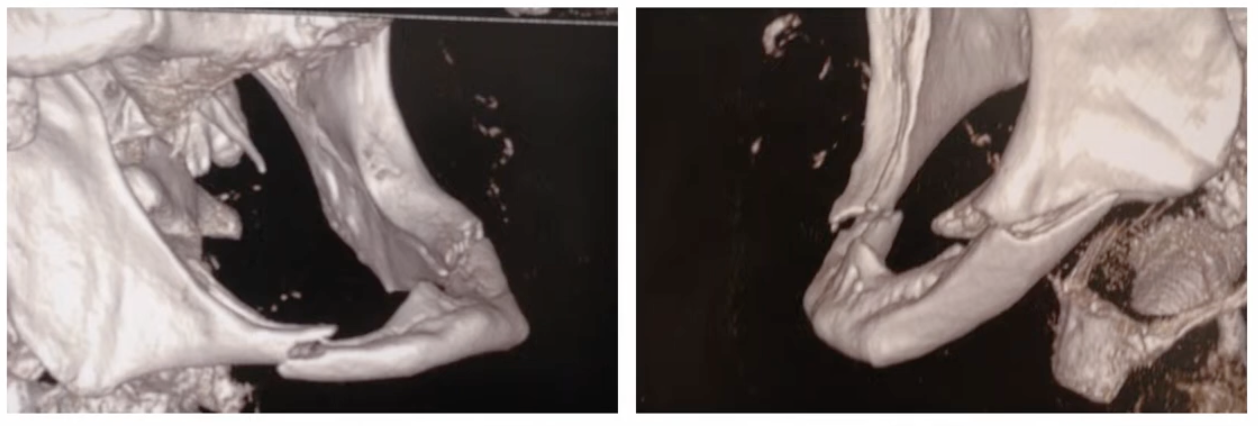

Comment appelle-t-on cette fracture ?

Fracture mandibulaire en anse de sceau, caractéristiques des patients édentés